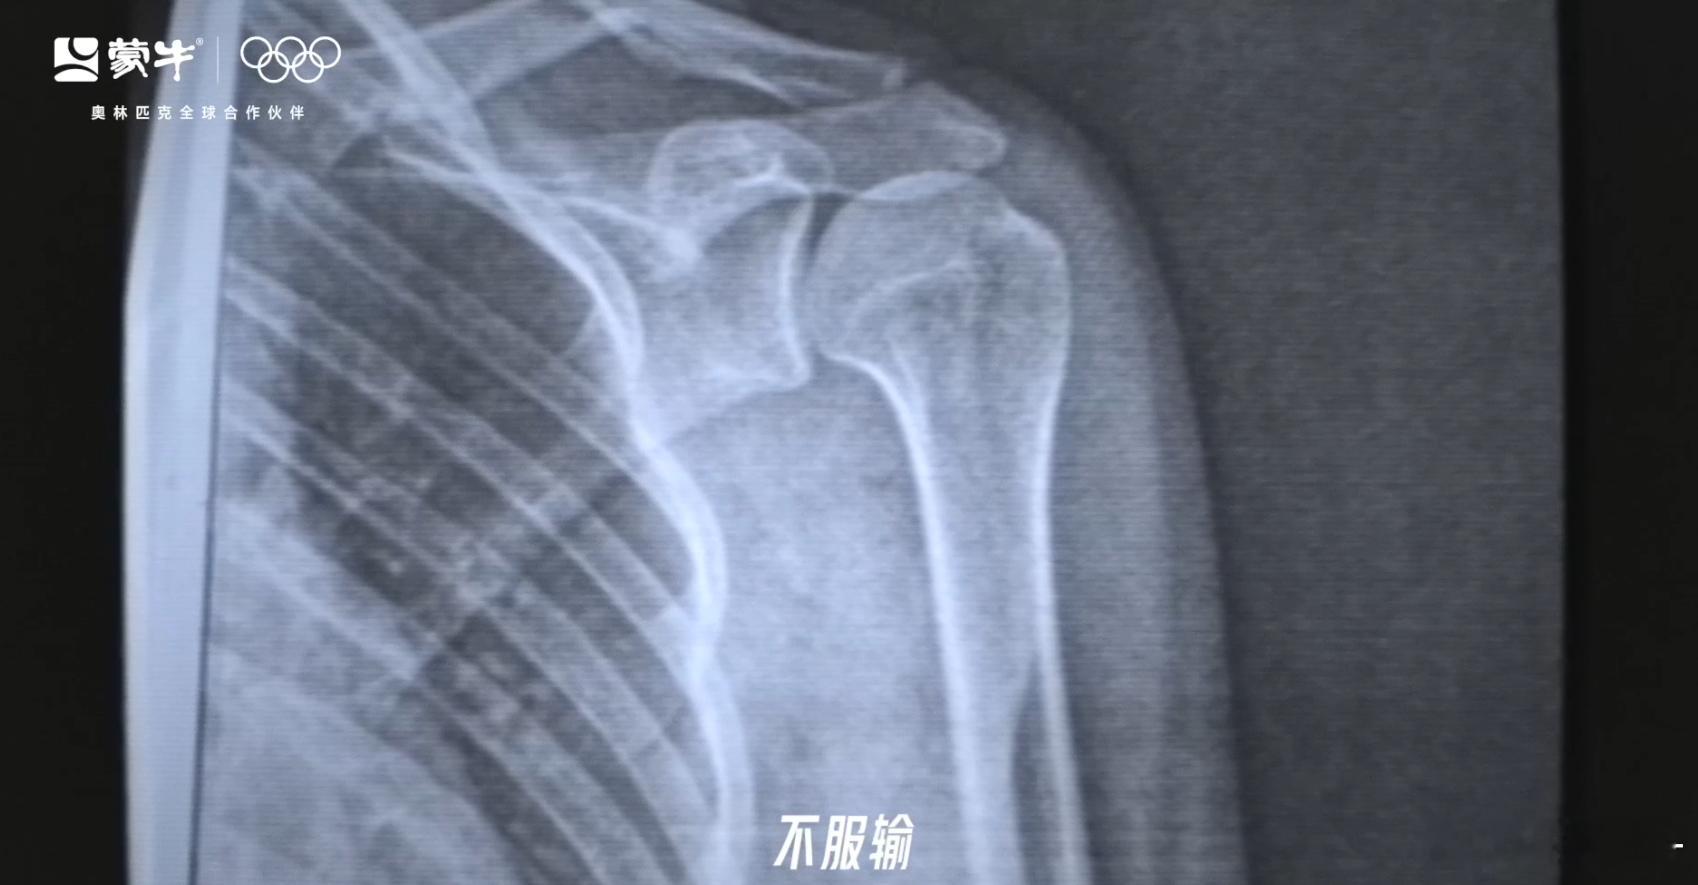

不管输赢,都一直把“拼搏”二字展现的淋漓尽致。谷爱凌的滑雪之路并非一帆风顺,摔倒、受伤、康复、再战!如果没有一颗要强的心,谷爱凌是不会取得这么成功的成绩的!